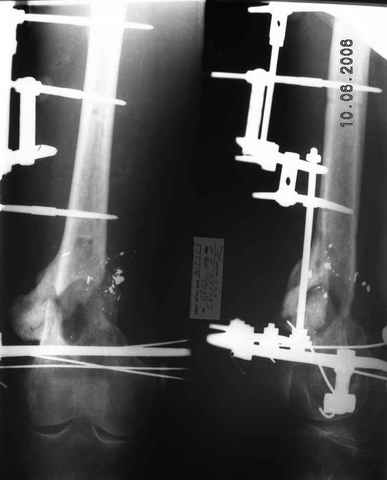

Рефрактур уж точно можно будет не опасаться, а за несколько месяцев даже при отсутствии заполнения костью по всей окружности, этот обходной "мостик" упрочнится и возьмет на себя нагрузку. В приложении пример такого рода "эндопротезирования диафиза", прошло больше 3 лет.

Пациентка, страдающая еще и инсулинозависимым диабетом, не хромает, работает инженером.